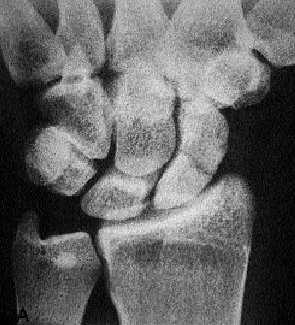

Radiología

El diagnóstico radiológico de esta fractura es engañoso porque en ocasiones las radiografías iniciales no demuestran ninguna lesión (ocurre en fracturas no desplazadas). Al producirse reabsorción ósea en el foco de fractura por el proceso inflamatorio y reparador, las radiografías obtenidas 10-15 días después demuestran la fractura (fig. 11).

Fig. 11. Fractura de escafoides.

Por otra parte, lo más frecuente es que se trate de fracturas sin desplazamiento, que resultarán difíciles de ver en este pequeño hueso del carpo. Por este motivo, el estudio radiológico debe efectuarse con las denominadas «proyecciones de escafoides carpiano», que incluyen una proyección dorsopalmar, una lateral y dos oblicuas de la muñeca.

La pauta de actuación que proponemos es que ante un traumatismo de muñeca con dolor localizado en la tabaquera anatómica y radiología normal deberemos tratarlo como si fuese una fractura de escafoides, es decir, con inmovilización en un yeso antebraquiopalmar que incluya el pulgar hasta la articulación interfalángica. Y deberá remitirse al traumatólogo para nuevo estudio radiológico (sin yeso) pasadas al menos dos semanas.

En cualquier caso que exista sospecha clínica de fractura y las radiografías sean negativas es aconsejable colocar un yeso incluyendo el pulgar y realizar una nueva exploración clínica y radiológica a las cuatro semanas.

Lo que permite establecer el diagnóstico es la existencia de una separación anómala entre el polo proximal del escafoides y el semilunar en la radiografía dorsopalmar. Se considera que toda separación mayor de 6 mm es diagnóstica.